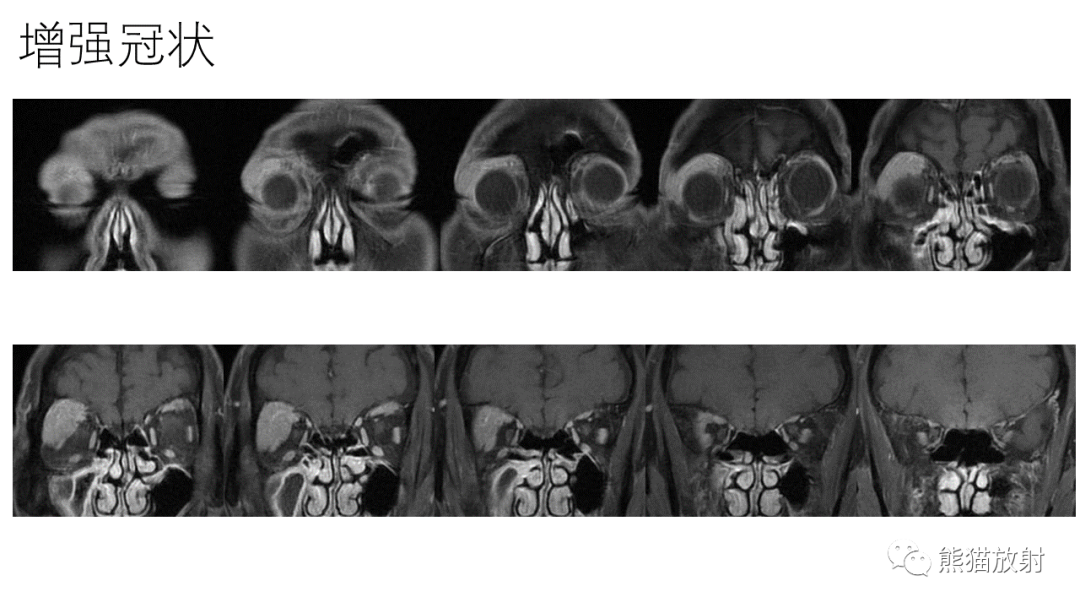

【PPT】泪腺多形性腺瘤 VS 眼眶淋巴瘤-2